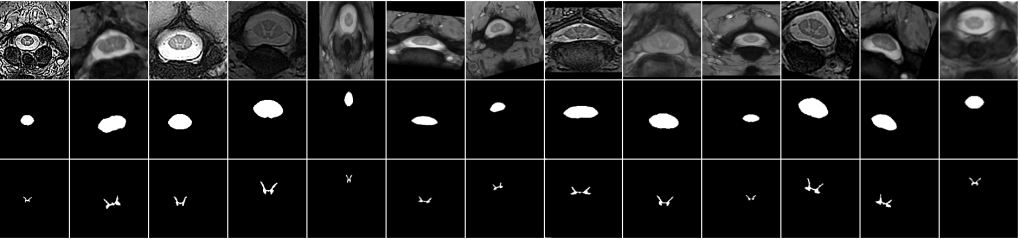

We further show some qualitative results in Figure 1. As we can see, while the “DeepAll" baseline as well as other domain generalization based methods fail to segment the gray matter (e.g. when using “site2" as target domain) or over-segment a large portion of gray matter by extending the segmentation maps to the white matter (e.g. when using “site3" as target domain), our proposed method can generally achieve better performance compared with all the methods for comparison.

Refer to caption

Figure 1: Qualitative comparisons. Each row represents a sample from a specific domain. Each column denotes the input, ground truth (gt) or different methods including DeepAll, CCSA [39], MLDG [21], MASF [7], Probabilistic U-Net [19] (abbreviated as PROB here), respectively. As the area of interest in the original samples is very small, all the samples are center cropped for better visualization.